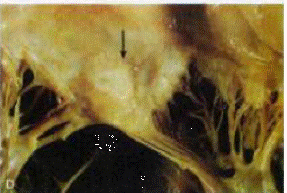

In corso di febbre reumatica:

disseminazione di lesioni

infiammatorie, a focolai, in numerosi organi e tessuti. Le più caratteristiche

lesioni cardiache sono i corpi di Aschoff. Essi sono formati da aree di

necrosi fibrinoide, circondati da linfociti, macrofagi, occasionali

plasmacellule ed istiociti rigonfi

attivati, chiamati cellule di Anitschkow e di Aschoff.

A livello del miocardio: corpi di Aschoff sparsi nel connettivo interstiziale

A livello dell'endocardio e delle valvole cardiache: focolai infiammatori con struttura differente. Sulle cuspidi e sulle corde tendinee: necrosi fibrinoide + vegetazioni friabili (verruche) lungo i margini di chiusura

VERRUCHE CARDIACHE: dovute a deposizione di fibrina a livello di erosioni endocardiche flogosate che vanno in contro a organizzazione.

Le lesioni subendocardiche possono dar vita inspessimenti irregolari: placche di MacCallun